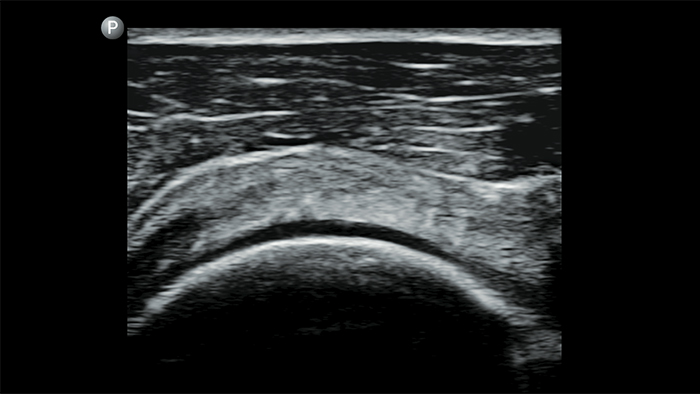

Utilice Lumify para la evaluación de las vías respiratorias y pulmonares

Las soluciones Lumify POCUS pueden ayudarle a detectar el tubo endotraqueal dentro de la tráquea, ayudar en los procedimientos de cricotirotomía emergentes, en el diagnóstico de derrame pleural y enfermedades alveolares intersticiales.